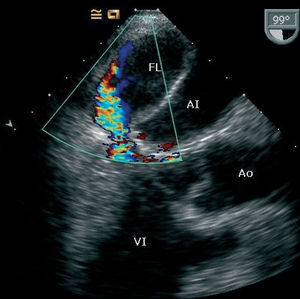

Al no haber correlación entre el ecocardiograma transtorácico y la situación clínica, se realiza un ecocardiograma transesofágico que revela una falsa cámara en el interior de la aurícula izquierda formada por la pared auricular posterior disecada, y que ocupa casi la totalidad del verdadero lumen (fig. 1). Se observa también flujo sistólico retrógrado en su interior proveniente de la pared posterior del ventrículo izquierdo por debajo de la prótesis. No se evidencia comunicación entre el verdadero y el falso lumen ni regurgitación perivalvular (fig. 2).

Fig. 2.